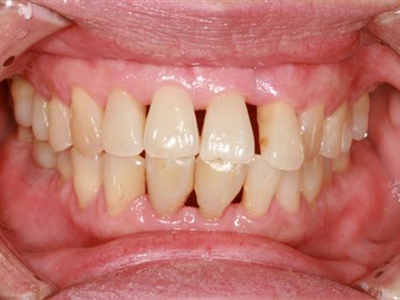

牙龈退缩牙齿出现三角形牙缝图

牙龈退缩表现为上排切牙、尖牙处牙龈发生回缩,导致牙龈暴露,并且牙齿发生松动,牙缝增大呈三角形,伴有口臭、牙根面敏感等症状。